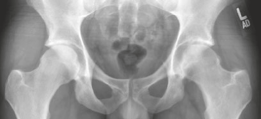

Standard anteroposterior (AP) pelvis and lateral hip radiographs are often the initial diagnostic step, but they may only show non-specific regional osteopenia or subtle cortical thickening in intra-articular cases.

High-resolution, thin-slice computed tomography (CT) with multiplanar reconstruction is the gold standard for defining the osseous anatomy. The CT scan accurately delineates the nidus as a well-circumscribed, radiolucent focus, often containing a central fleck of mineralization, surrounded by varying degrees of sclerosis. The surgeon must meticulously map the location of the nidus relative to reliable arthroscopic landmarks, such as the medial synovial fold, the zona orbicularis, and the articular margin of the femoral head.